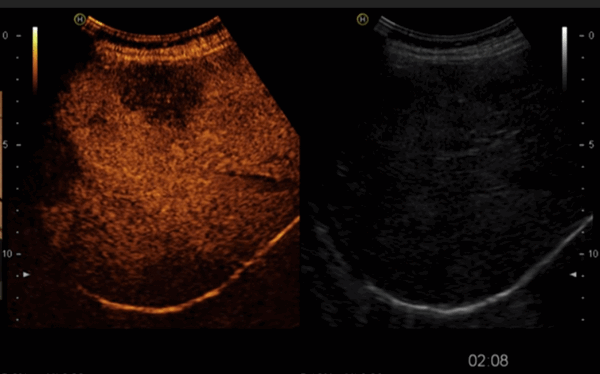

На снимках наглядно видно отличие от обычного УЗИ:

Режим эхоконтрастирования (слева) позволяет четко локализовать очаговое поражение печени.